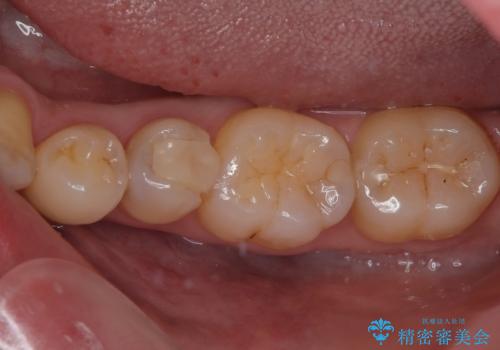

- 左下の奥歯のところがフロスが引っかかったり、ちぎれたりするとのことで来院された患者様です。検査の結果、神経は正常な反応を示し、フロスは引っかかる状態でしたので、虫歯治療も併せて行うためにオールセラミッククラウンによる補綴治療を行っていくことにしました。

拡大鏡視野下でプラスチックの詰め物、虫歯を除去しオールセラミッククラウンに適した形に整えました。